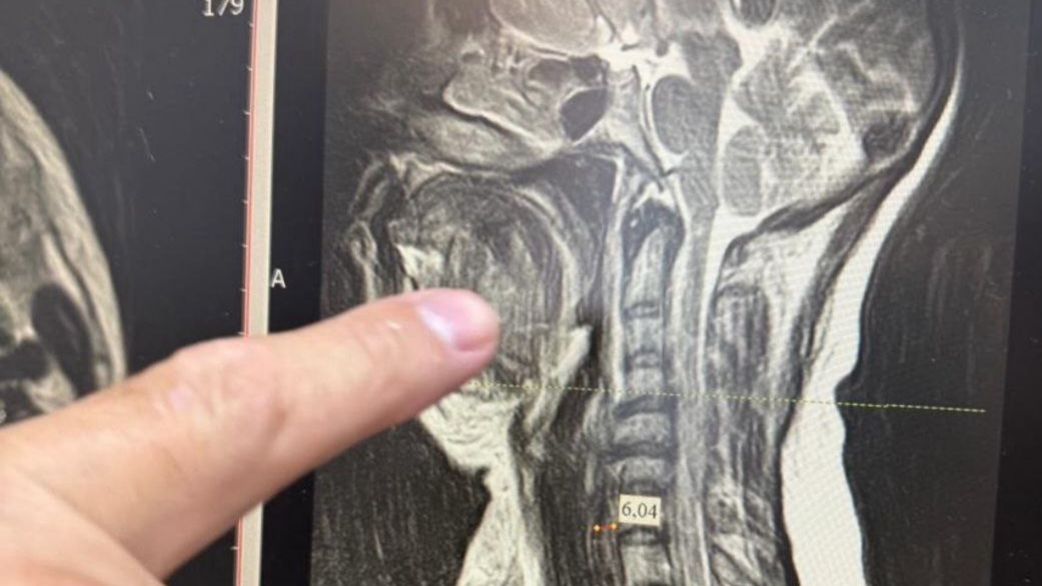

Медики столкнулись с одной из самых сложных форм осложнения – двусторонней флегмоной окологлоточного пространства, которая при отсутствии своевременного лечения в большинстве случаев заканчивается летальным исходом. Специалисты стали готовить женщину к экстренной операции. Из-за сильного отека тканей шеи невозможно было вставить трубку для дыхательного наркоза, поэтому работали через трахею.

Челюстно-лицевой хирург Шахбан Мисриев установил около восьми дренажей. Три дня пациентка провела в реанимационном отделении, подключенной к аппарату ИВЛ.